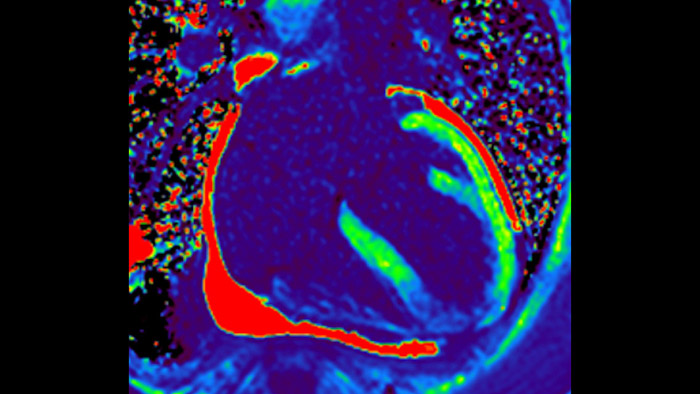

Today's diagnostics often cannot detect heart dysfunction until symptoms occur. MyoStrain utilises segmental strain to measure 48 segments of the heart and provides physicians with a unique diagnostic tool to help identify regional dysfunction before the heart as a whole is affected.

IntelliSpace Portal MR Caas5,6 Strain7 assists in patient diagnosis and monitoring by providing global strain parameters such as global longitudinal strain (GLS), global circumferential strain (GCS), and global radial strain (GRS), using short and long axis MR images, as well as describing the myocardium deformation- such as shortening, thickening, and lengthening during the cardiac cycle.